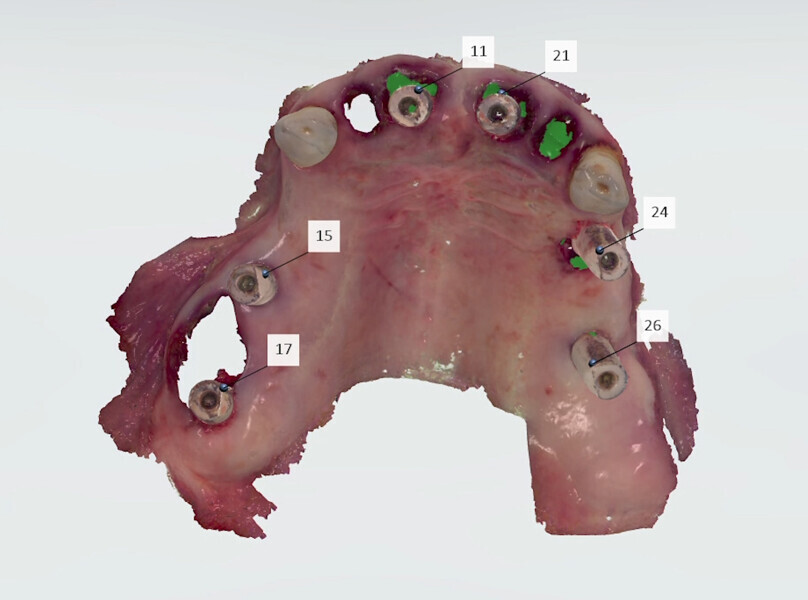

The fully digital Pro Arch protocol